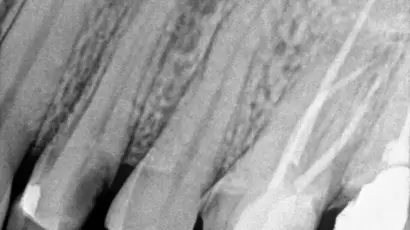

The X-ray revealed a dental abscess, where infection had started affecting the bone around the tooth. (X ray Picture)